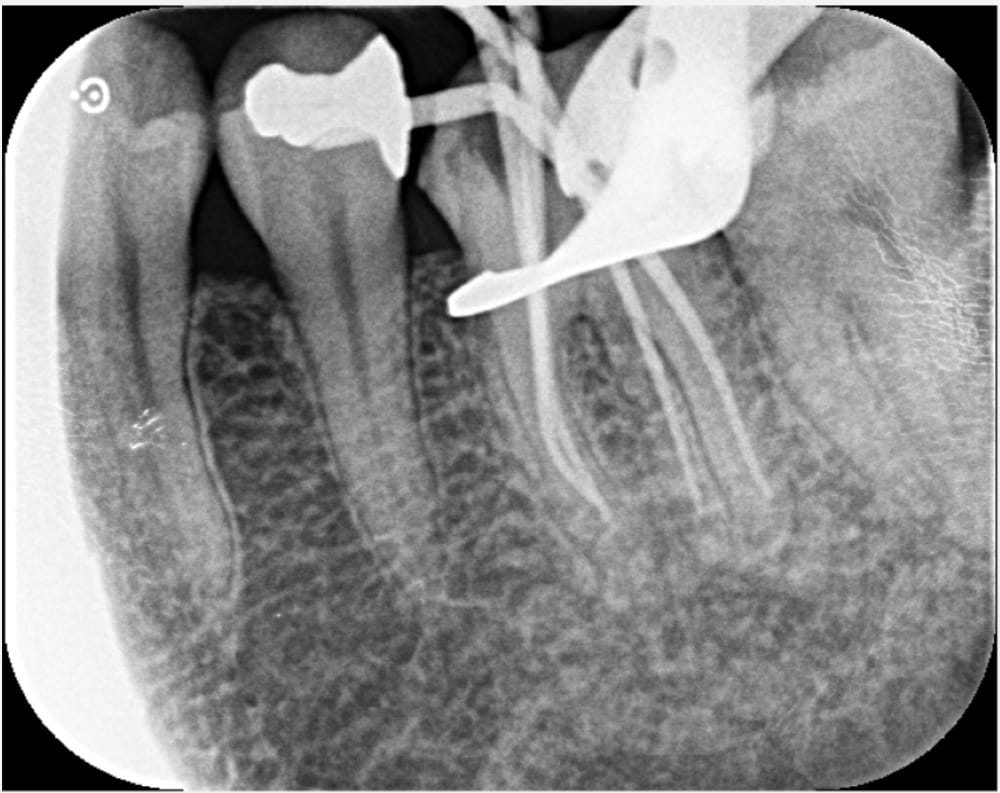

左下6番は仮封がされている状態であり、レントゲン画像では歯と封鎖材料の隙間がある状態でした。口腔内の所見からも、虫歯が残存していることが推測されました。痛みの原因としては、複数回のペリオドンの使用に加え、ラバーダムがない根管治療を受けていることや虫歯が残存していることなどが考えられます。

精密根管治療 1回目